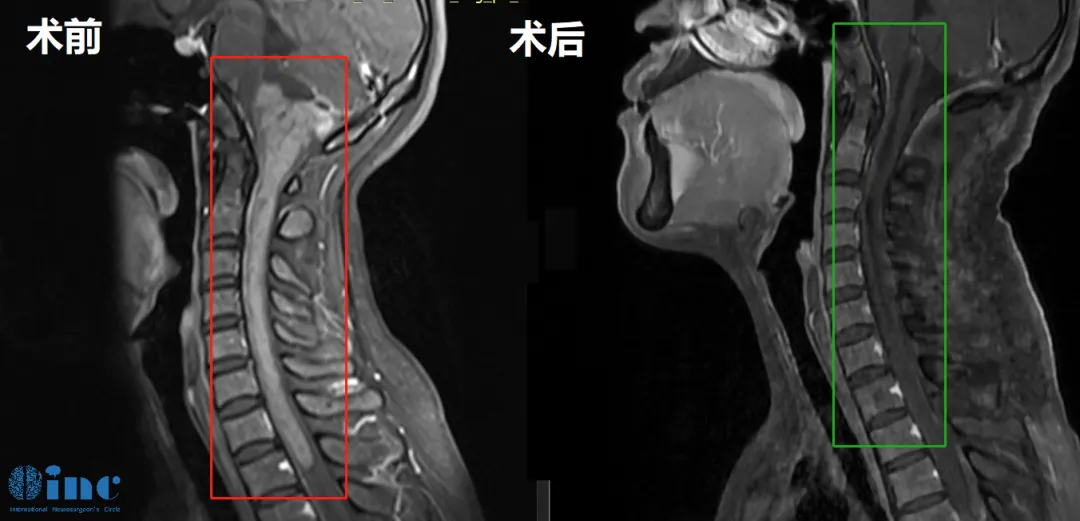

33岁女士-脊髓髓内室管膜瘤

33岁的郑女士2016年因晨起颈部疼痛和自感右上肢无力,提示颈椎椎管占位性病变,期间郑女士因为怀孕未行任何治疗。然而2021年前患者感到症状加重,肢体出现无力及麻木以及温度异常。2022年8月行核磁复查,病变较2017年范围明显增大,累及延髓和颅颈交界区,且向下方延伸到整个颈部脊髓以及一直到第一胸椎水平,病变累及范围近15cm。为了更好的陪伴着孩子的成长,郑女士决定寻求世界大咖的治疗……

▼巴教授术前术后影像对比

2022年11月巴教授疑难示范手术期间,2022年11月23日,这台长达12个小时的高难度手术在苏州独墅湖医院顺利完成,手术时长相当于两台手术——延髓和脊随髓内。

术后第12天查房,郑女士已经可以正常下地站立,肢体活动正常,除了右手稍微无力,术后3个月,在郑女士传来的康复视频里,她已经可以正常行走,术后无力的右手已经也可以正常抓握小物体、手部运动正常。